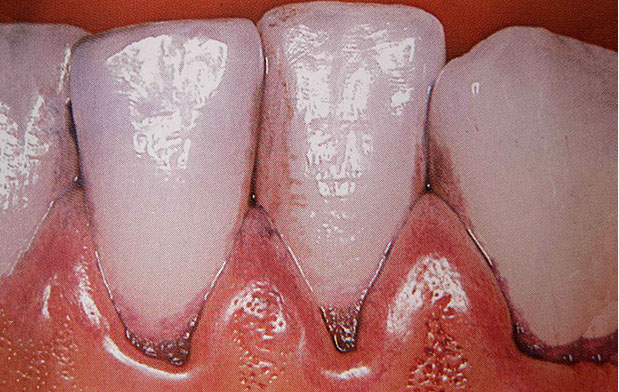

Before the actual cleaning, a detailed dental status is recorded. A staining solution is often applied to make hidden plaque visible to the patient. We are happy to take intraoral enlargements (photographs) for our patients to motivate them and to show concealed problem areas. You can only see what you know.

In the first step of cleaning, tartar and plaque are removed from the teeth using ultrasound and Airflow®. The spaces between the teeth are then flossed and cleaned.

Solid deposits, which often form below the gingival margin, are gently removed with special instruments. Gum pockets are also rinsed and disinfected.